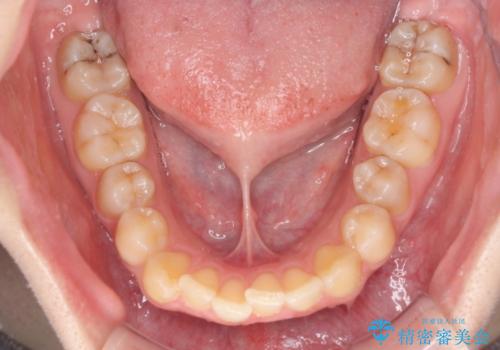

前歯のデコボコをインビザライン矯正で綺麗に改善

- 上下前歯のデコボコを気にして来院された患者様です。

全体的に叢生は軽度であったため、インビザラインにて矯正治療を行うこととしました。

舌の突出癖改善がうまくいかず、途中で舌小帯の切除を行いました。

気になる段差を納得いくまで改善させたため、治療期間は長くなりましたが、綺麗な仕上がりとなりました。